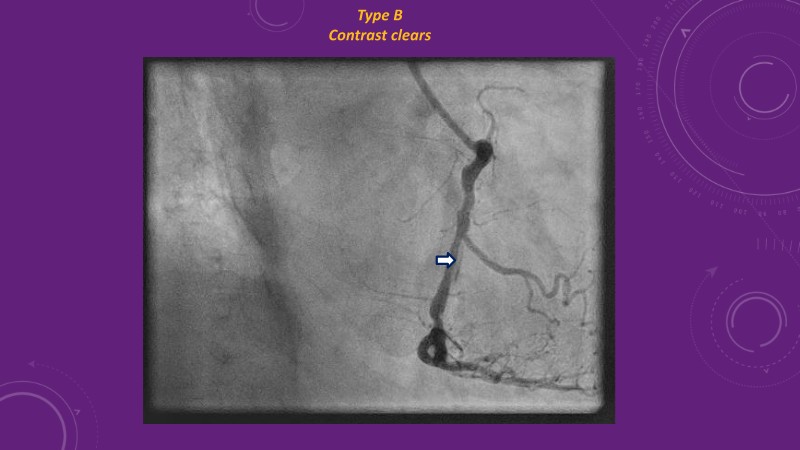

Explore cutting-edge strategies for optimizing drug-coated balloon (DCB) procedures in this session. Uncover practical tips to improve outcomes, review key indications, and examine international consensus on DCB use. Case presentations and expert discussions offer insights to refine your approach.